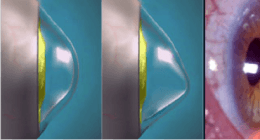

Il cheratocono è una malattia non infiammatoria che comporta una progressivo aumento di curvatura della cornea ed assottigliamento con deformazione della stessa. La malattia ha carattere progressivo con velocità di evoluzione molto variabile da caso a caso, maggiore comunque nei soggetti giovani.

Il Cross-linking del collagene corneale è una terapia innovativa che sfrutta una sostanza innocua, la Riboflavina, nota come Vitamina B2, per creare una reazione chimica all’interno dello stroma corneale, innescata dalla luce ultravioletta emessa da una lampada appositamente studiata (Apparecchio Vega). La reazione comporta un moltiplicarsi di legami tra le fibre collagene che diventano più spesse, più ordinate e più resistenti a stimoli meccanici e chimici. Ne risulta una stabilizzazione della cornea con conseguente arresto dello sfiancamento della stessa e, pertanto, dell’evoluzione del cheratocono.